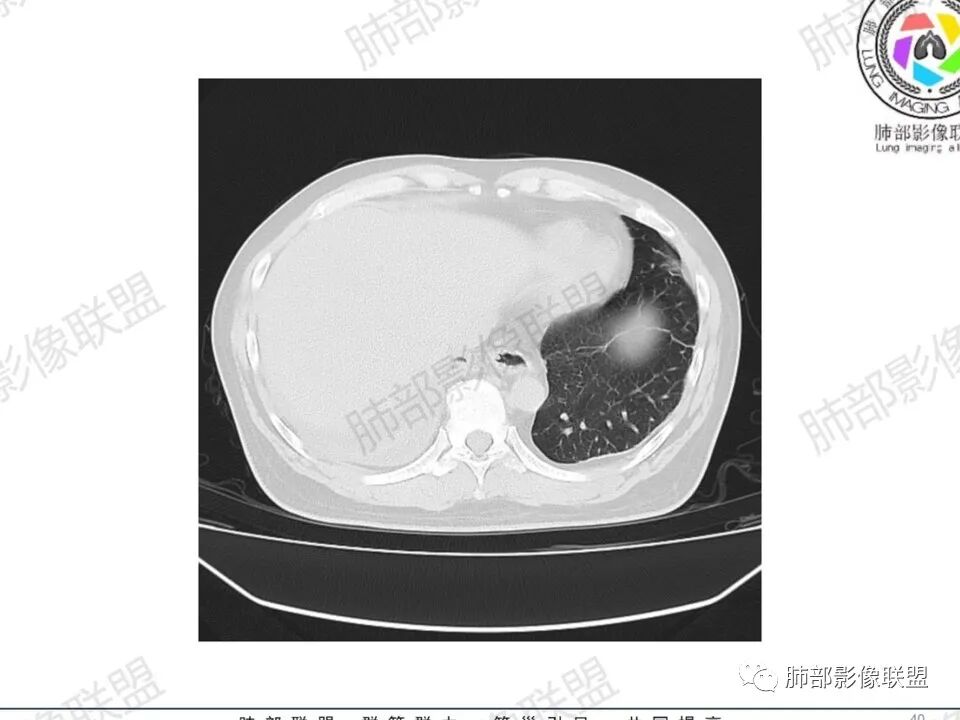

双肺多发结节,胸膜下为主,部分可见空洞。左肺上叶尖后段结节较大,分叶毛刺,周围可见长条索及小斑片影,内空洞比较光滑,内侧壁可见支气管通过。右肺下叶后基底段不张实变,后侧积液,右侧水平裂积液,右侧膈胸膜纵膈胸膜增厚积液,右侧侧胸膜肥厚,考虑1:一元金葡。2二元:金葡,左肺上叶结核。

男,45岁,左手指红肿疼痛两天,右侧胸壁疼痛伴发热12小时入院。患者急性起病,胸部CT示双肺多发结节,部分伴空洞,空洞壁较光滑,右侧胸腔积液,考虑感染性病变,金葡菌加SPE可能

尘缘: @赵永兵 内蒙巴市临河妇幼影像科 左上肺也是胸膜下(胸膜顶下)的SPE。

@赵永兵 内蒙巴市临河妇幼影像科 支气管是从旁边经过,所以不是空洞,是胸膜下的脓毒栓。如果是结核空洞,应该与支气管相通(因为结核没有血播感染表现的时候,来源是气道,空洞应该与支气管相通),所以支气管从旁边经过,这病灶又在胸膜下,周围也没有干酪坏死。当然是SPE了。

中年男性,左手中指及胸壁疼痛伴发热来诊,影像见双肺多发结节,胸膜下分布为主,部分结节可见空洞,边缘模糊。左肺上叶尖后段结节较大。右肺下叶后基底段不张实变,右侧叶间裂及右侧胸腔积液,右侧侧胸膜肥厚。考虑金葡菌感染,血播SPE。

空洞内壁光滑,偏心厚壁空洞,张力高